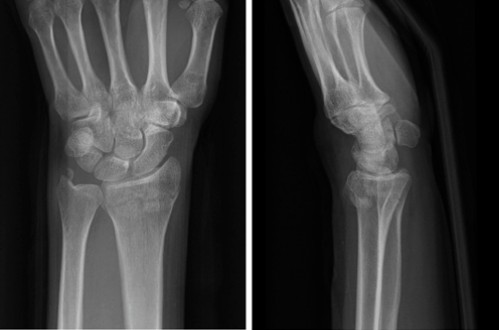

Случай ①